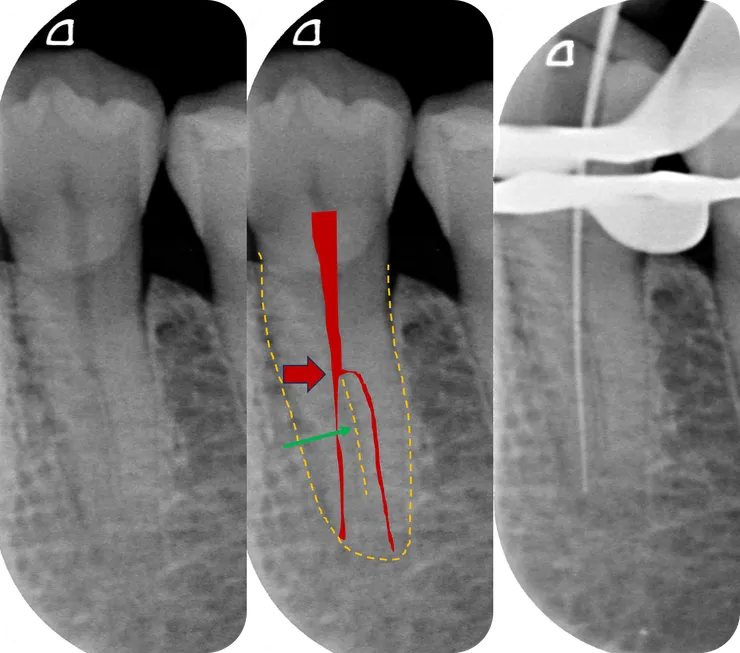

除此之外,deep split canal 發生在 lower-premolar 時,還有一個惡名昭彰的特徵,那就是如中圖紅色區域所示的 "h 形分岔"!

打開之後可以看到,紅色箭頭所指的亮點是轉診醫師找到的 buccal canal.

從 access cavity 的型態看得出來轉診醫師有試著去尋找 lingual canal. 但要找到 h 形的分岔是相當困難的!然後更困難的是找到之後的 C&S......

Shaping 大致完成後長這樣:

左下較黑處是個 ledge.

綠色箭頭所指的白洞是 buccal canal.

紅色箭頭所指的是 #10 C-pilot 彎進 lingual canal 的樣子。

面對這樣接近直角的入口彎度,必須把對付 [ curved canal ] 的技巧拿來運用: